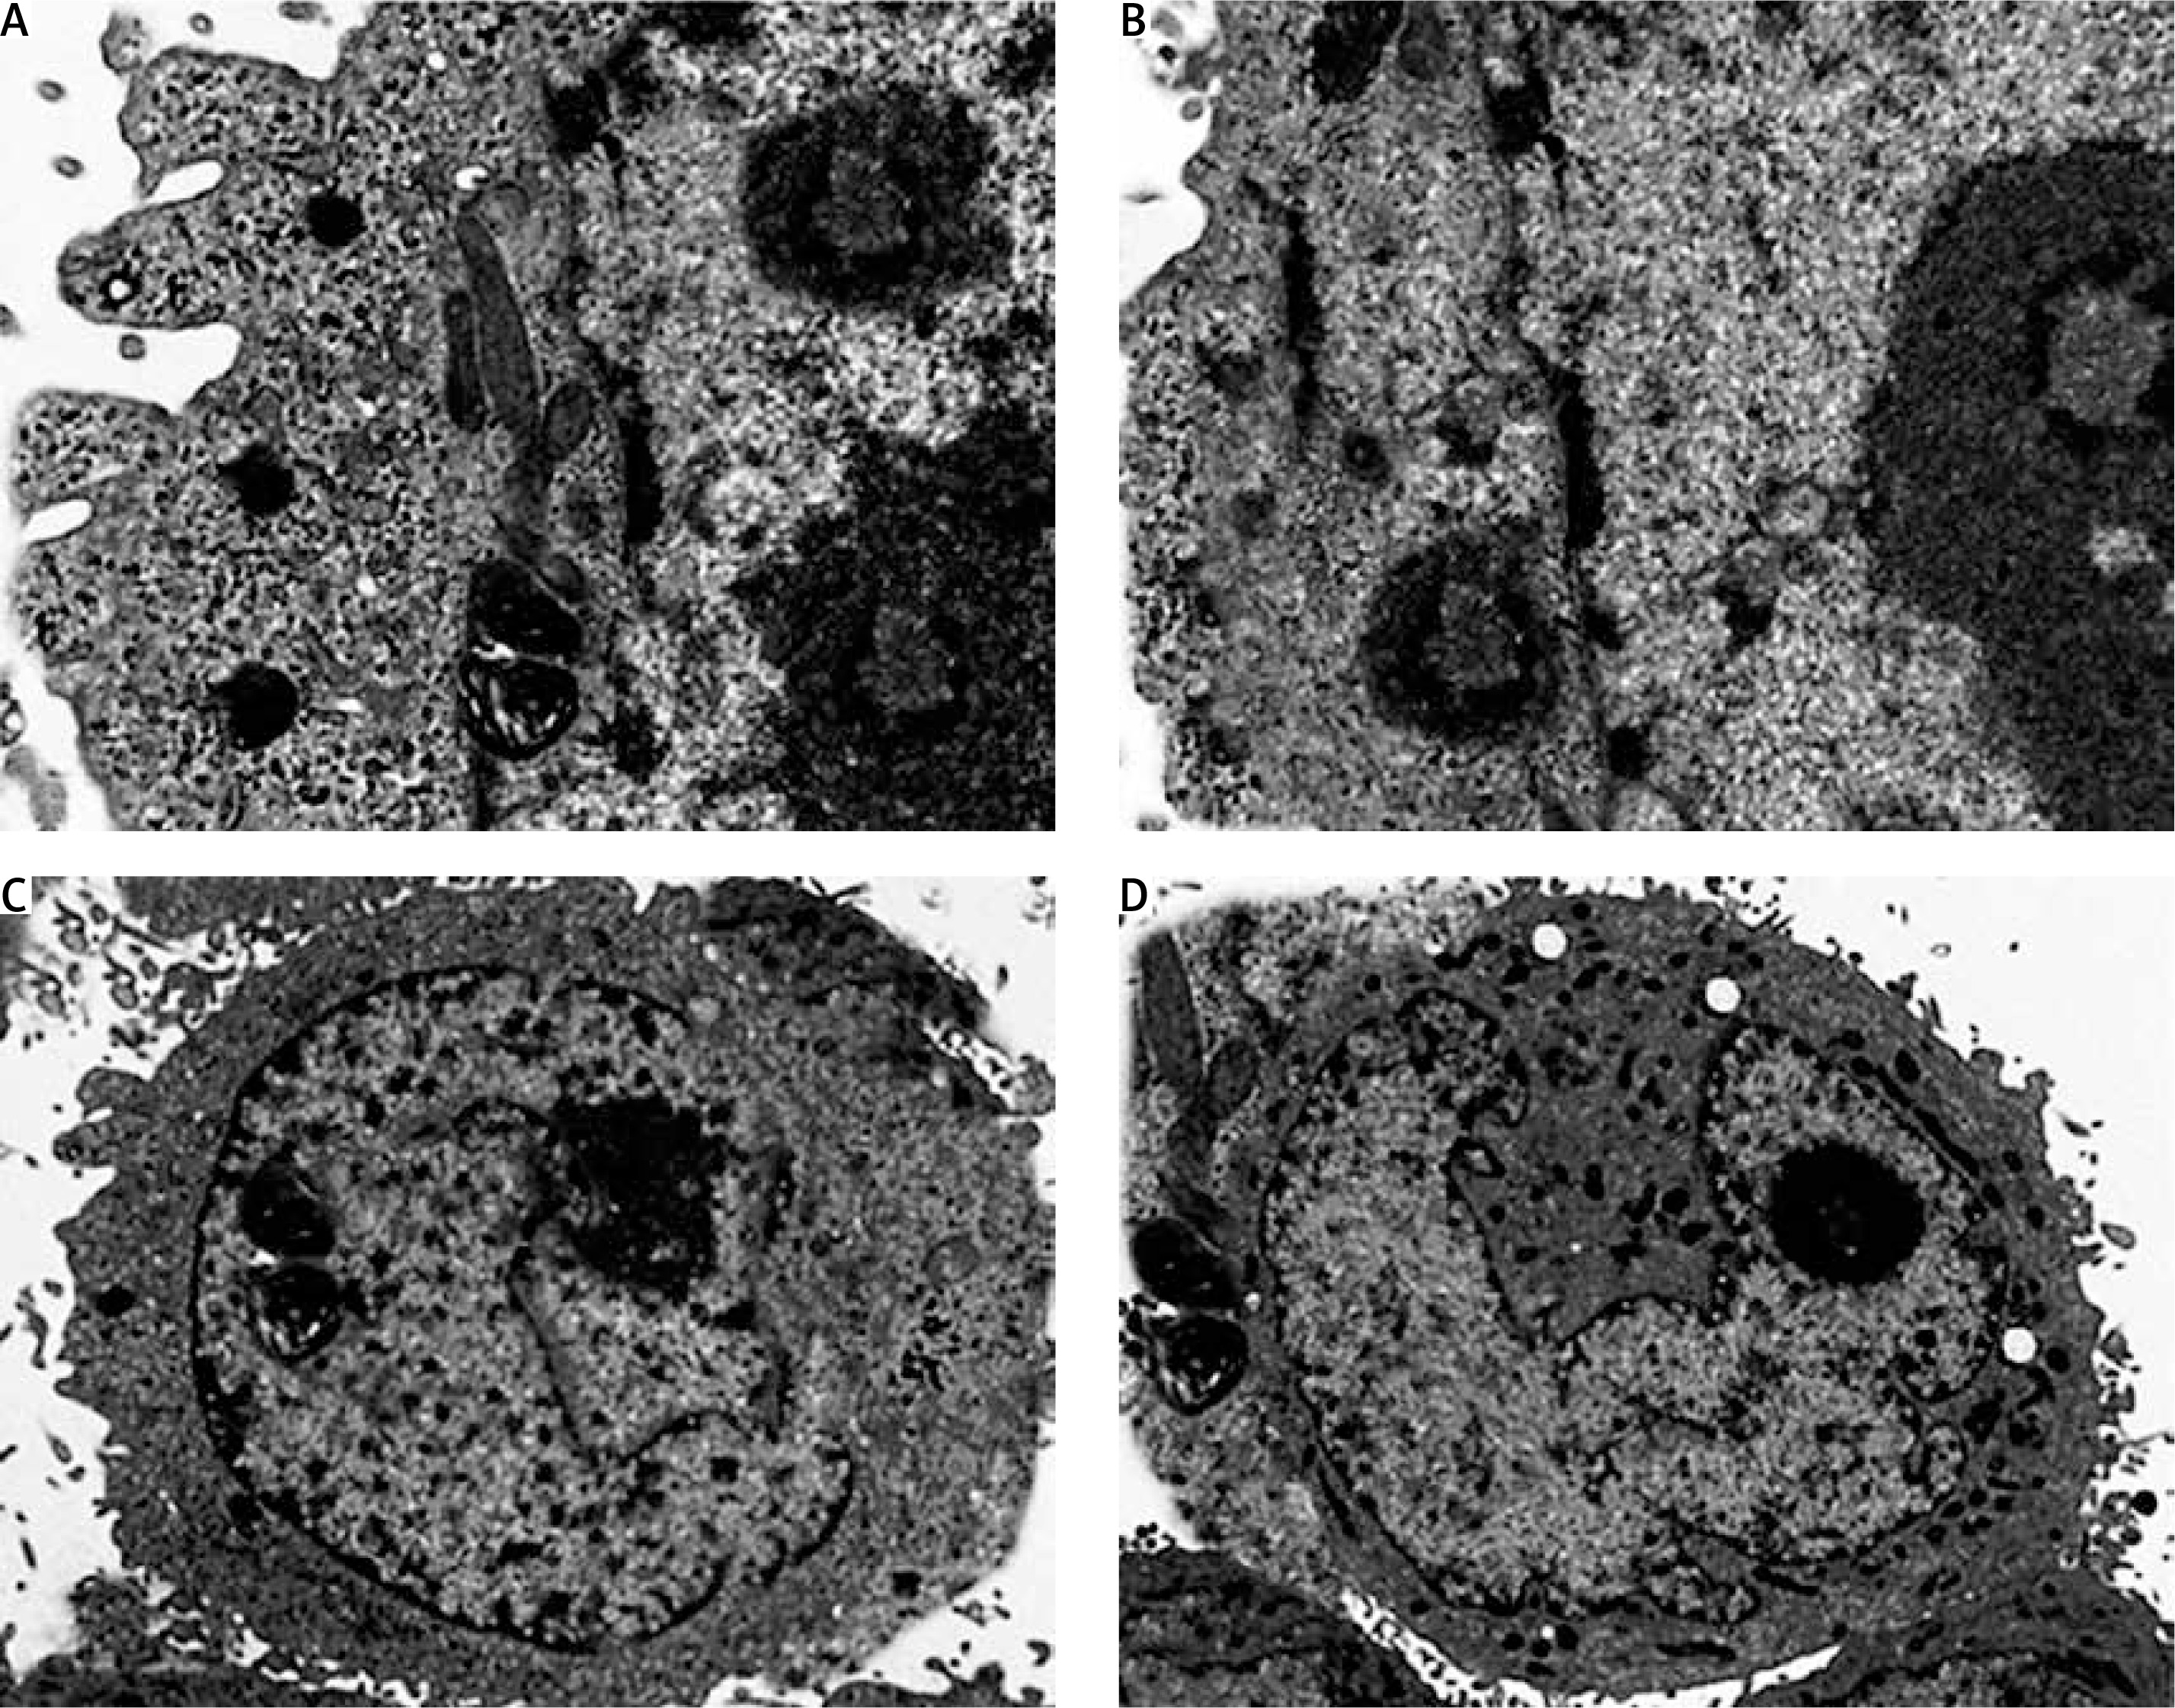

The fact that dehydrocostus lactone induces apoptosis in BON-1 cancer cells was further confirmed by using TEM. The results of this observation are shown in Figures 4 A–D. Control cells (untreated cells) exhibited normal ultrastructure with round nuclear membrane, normal mitochondria and the nucleolus present within the nucleus (Figure 4 A). But, after the cells were treated with 5, 50 and 100 μM concentrations of dehydrocostus lactone for 48 h, the mitochondria were destroyed, chromatin condensation occurred and the nuclear membrane disappeared. This was accompanied by the appearance of vacuoles in the cytoplasm, which is a hallmark of early apoptotic events which was clearly absent in untreated control cells (Figures 4 B–D). Thus TEM results confirm the results of fluorescence microscopy, which indicates that dehydrocostus lactone induces apoptosis in BON-1 cancer cells.

Figure 4

Transmission electron microscopy (TEM) analysis for evaluating the effect of dehydrocostus lactone on the apoptosis induction in BON-1 cells. A – Untreated control group, B–D –cells treated with 5, 50 and 100 μM dose of the compound (cells were observed at 8000× magnification). Appearance of vacuoles at higher doses is a sign of an early apoptotic event. All images are representatives of three biological replicates